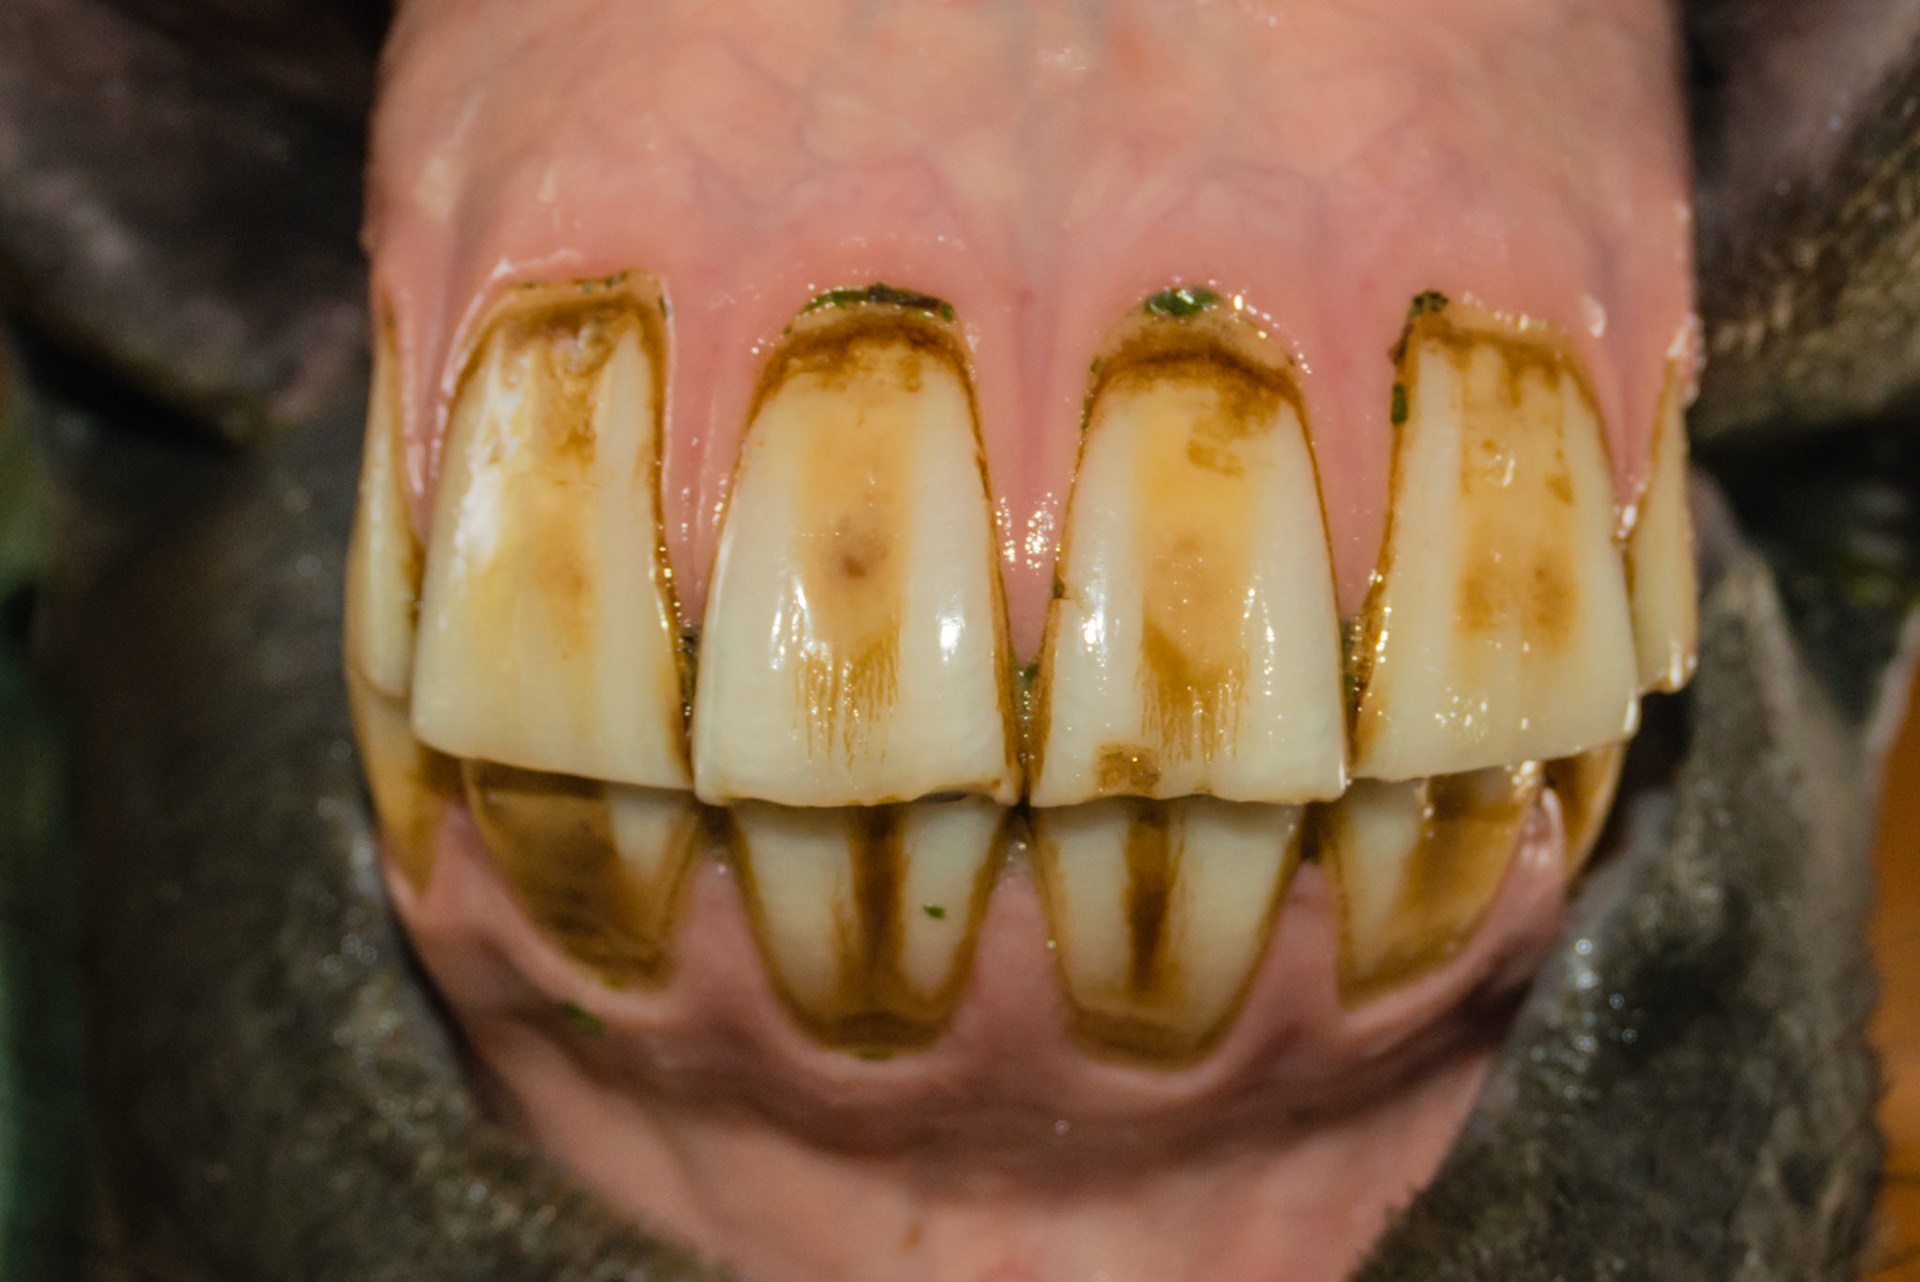

6yr old  Damaged and stained surfaces of all incisors.  Unknown history.